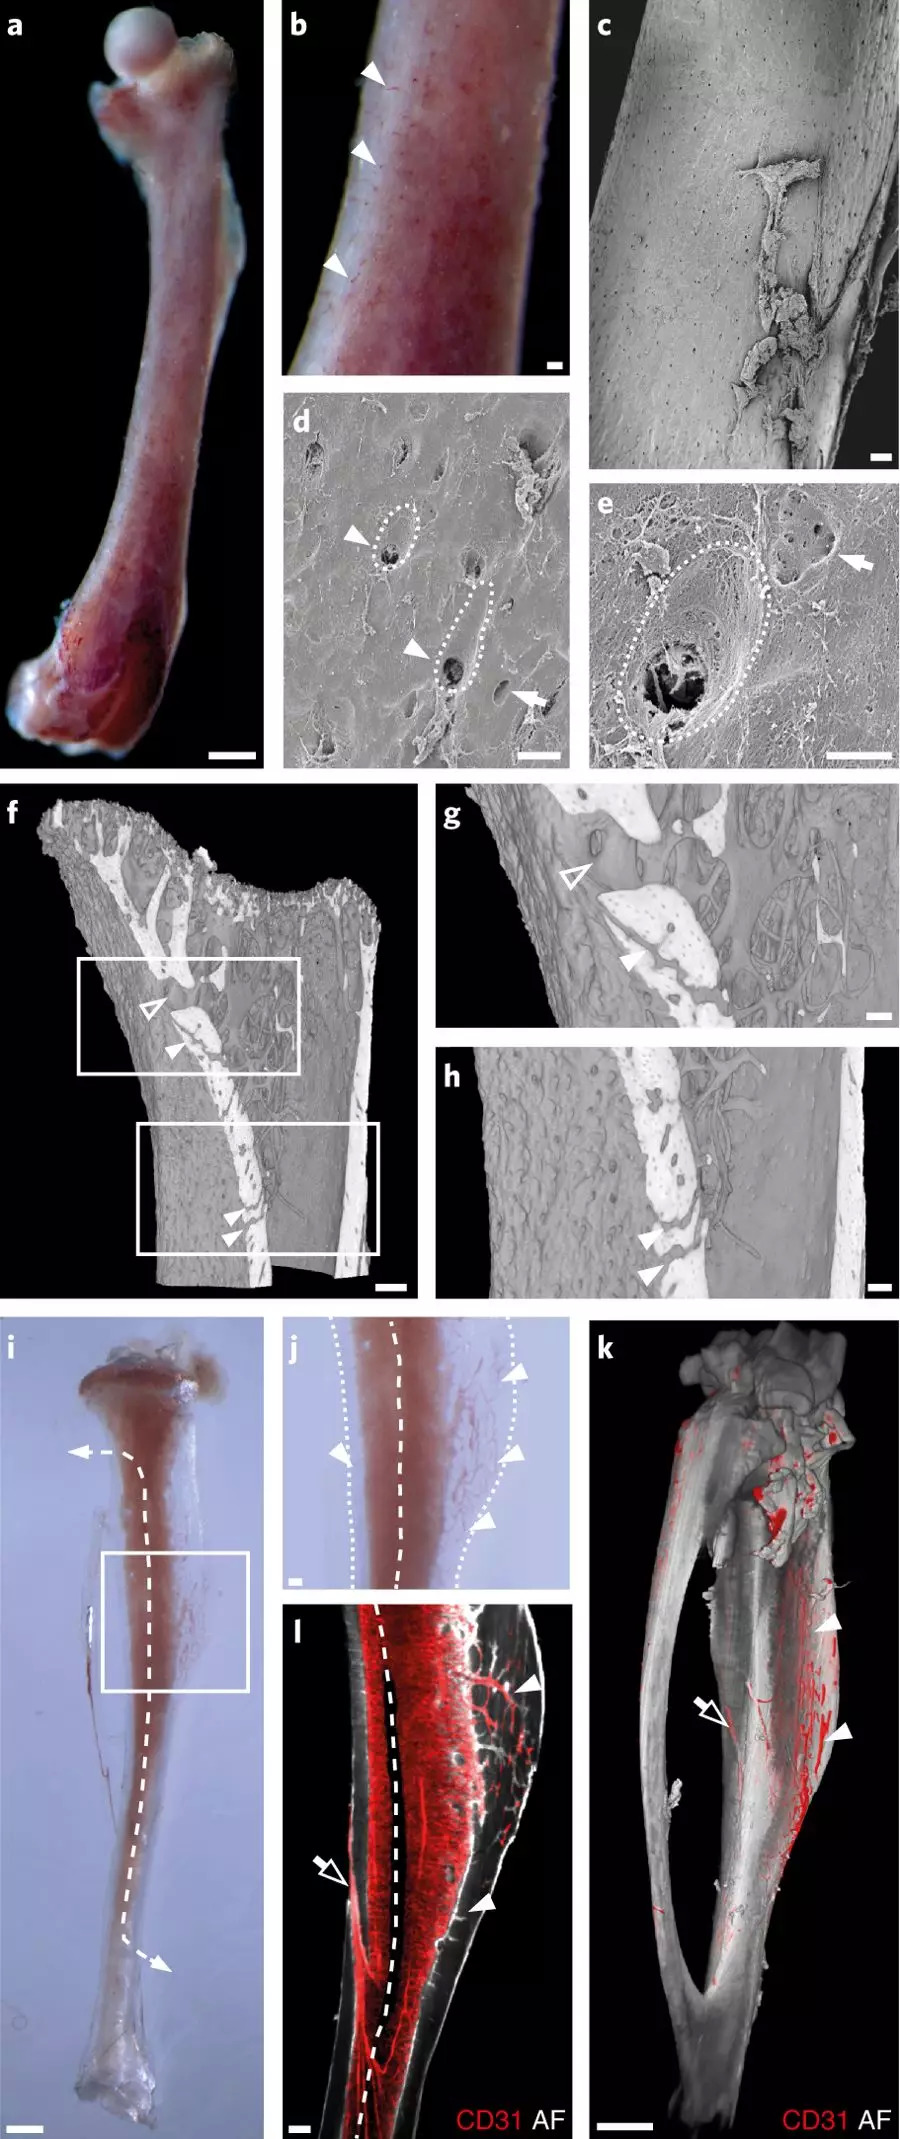

Gunzer的团队做出这一发现的起始是利用化学物质使实验小鼠的骨骼变透明,通过观察这些透明的骨骼,发现有细细的红色微小血管从骨干中穿过。

实验动物的小腿骨大概只有一根火柴那么大,但是在这样一根细小的骨头里,他们发现了大约一千根这样的细血管,并将其命名为跨皮质血管。在此之前,学界一直认为只有少量血管的末端或中段会跨越骨骼进入骨腔内,但在这个新发现中,研究团队看到这些跨皮质血管覆盖了整个骨骼,并且给骨骼供应了大部分血液。

图片来自 nature metabolism

人体当中也存在类似的跨皮质血管,该研究团队在小块的人大腿骨中也发现了它们的存在。由于还有其它的血管给人体骨骼供血,因此跨皮质血管可能占总循环量的比例较小,不过到目前为止还没有人计算过人体骨骼当中到底有多少这样的血管存在。

Gunzer表示,在骨骼当中,骨髓是产生免疫细胞的地方。在小鼠体内,他们发现跨皮质血管是输出免疫细胞的重要途径,那么人体中,很可能也是类似的机制。